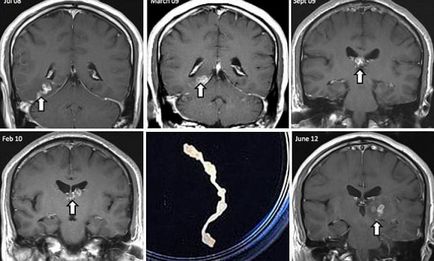

Ez az első alkalom a férfi megfordult, hogy az orvosok négy évvel ezelőtt, ő fejfájásra panaszkodott, és furcsa szagot. Az orvosok, akik végzett felmérés, megzavarodtak kóros területeket az agyban, hogy az MRI kimutatta. Megfigyelések a következő években azt mutatta, hogy a rendellenesség által mozgatott öt centiméter, írja a The Guardian.

Az orvosok a St. Thomas Kórház beteg HIV-tesztet, a szifilisz és a különböző fertőző betegségek. Ennek eredményeként, a biopszia jelenlétét mutatta galandféreg. Genetikai Wellcome Trust Sanger Institute Cambridge megállapítottuk, hogy ez egy rendkívül ritka parazita ismert Spirometra erinaceieuropaei.

Dr. Haley Bennett azt mondja, hogy a kapott genetikai anyag lehetséges, hogy a jövőben ilyen esetekben diagnosztizálni, és megkönnyíti a fejlesztés egy kezelést. „Elég furcsa féreg, és nem tudjuk, hogy mindent róla az emberek túl ritka házi neki.” - idézett egy orvos a Daily Mail. A kapott információ kerül át a nemzetközi bázis paraziták.